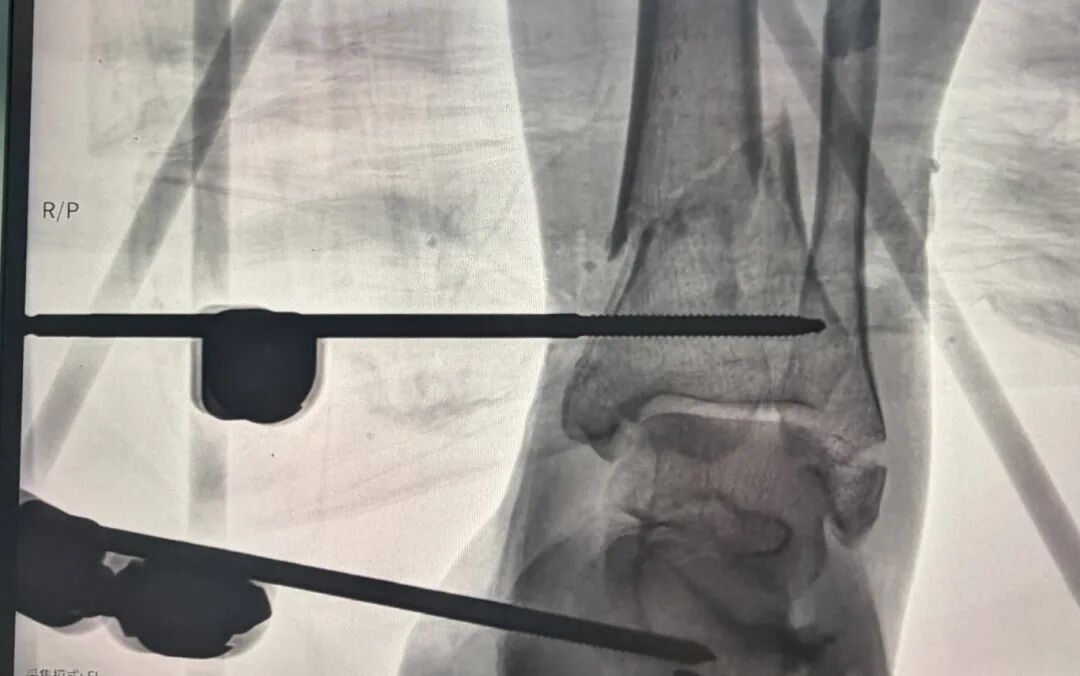

“右下肢保肢无望,必须果断截肢保命!”尹绍猛教授一声令下,立即带领骨科团队行动,结合患者休克病情,果断敲定“右下肢截肢保命、左下肢清创保肢”的核心方案。术中,患者血压突然持续下降,考虑为截肢后再次失血所致,尹绍猛教授临危不乱,立即指挥骨科团队实施右侧股动脉穿刺,置入腹主动脉阻断球囊(放置位置平腰3)。球囊充气后,患者血压逐渐回升,成功化解术中危机。

在患者大出血、休克濒死的极端状态下,骨科团队凭借精湛的微创操作技术,快速阻断腹主动脉血流,为截肢手术创造“无血视野”,将术中出血量严格控制在800ml以内,成功避免患者因再次大出血死亡。